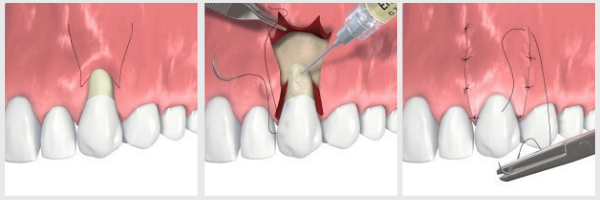

Mint minden fogorvosi-parodontológiai kezelés, az ínyplasztika is helyi érzéstelenítéssel kezdődik. Ezután megtörténik a szituációnak megfelelő lebenyképzés. A graftanyag behelyezése után a lebenyt finom varratokkal rögzítjük. Amennyiben a szájpadlásból történt a graft kivétele, úgy a szájpadlásra egy sebvédő pakolás kerül rögzítésre.

Az ínyplasztikai eljárások menete röviden:

- érzéstelenítés

- lebenyképzés

- graftanyag rögzítése

- varratok behelyezése